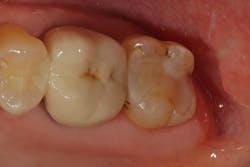

Lastly, the restoration is contoured into its final anatomical form and polished. The highly filled composite not only has excellent esthetics, but it will also achieve a high polish and demonstrate a very low wear rate over time (figure 4).